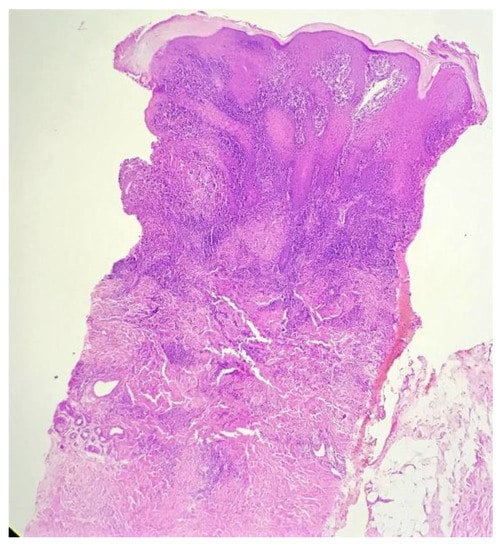

Biopsy showed a dense lichenoid and loose tuberculoid granulomatous infiltrate comprising of epithelioid cells, histiocytes and occasional Langhan’s giant cells, surrounded by lymphocytes and few plasma cells. The granuloma was seen abutting the overlying epidermis, which showed psoriasiform hyperplasia with mild to moderate spongiosis. A compact tuberculoid granuloma was also seen in the deep reticular dermis. Fibroplasia was also seen in the dermis (Figure 2, Figure 3, Figure 4 and Figure 5). The PAS-stained sections were negative for fungal organisms. Zeil–Neelsen stained sections did not reveal any acid-fast bacillus. Based on these features, a diagnosis of lupus vulgaris was favoured and further confirmation by culture study and PCR was advised.

Figure 2. Lichenoid granulomatous dermatitis pattern with psoriasiform epidermal hyperplasia (H&E × 40).

Figure 3. Loose tuberculoid granuloma abutting the overlying hyperplastic epidermis (H&E × 100).